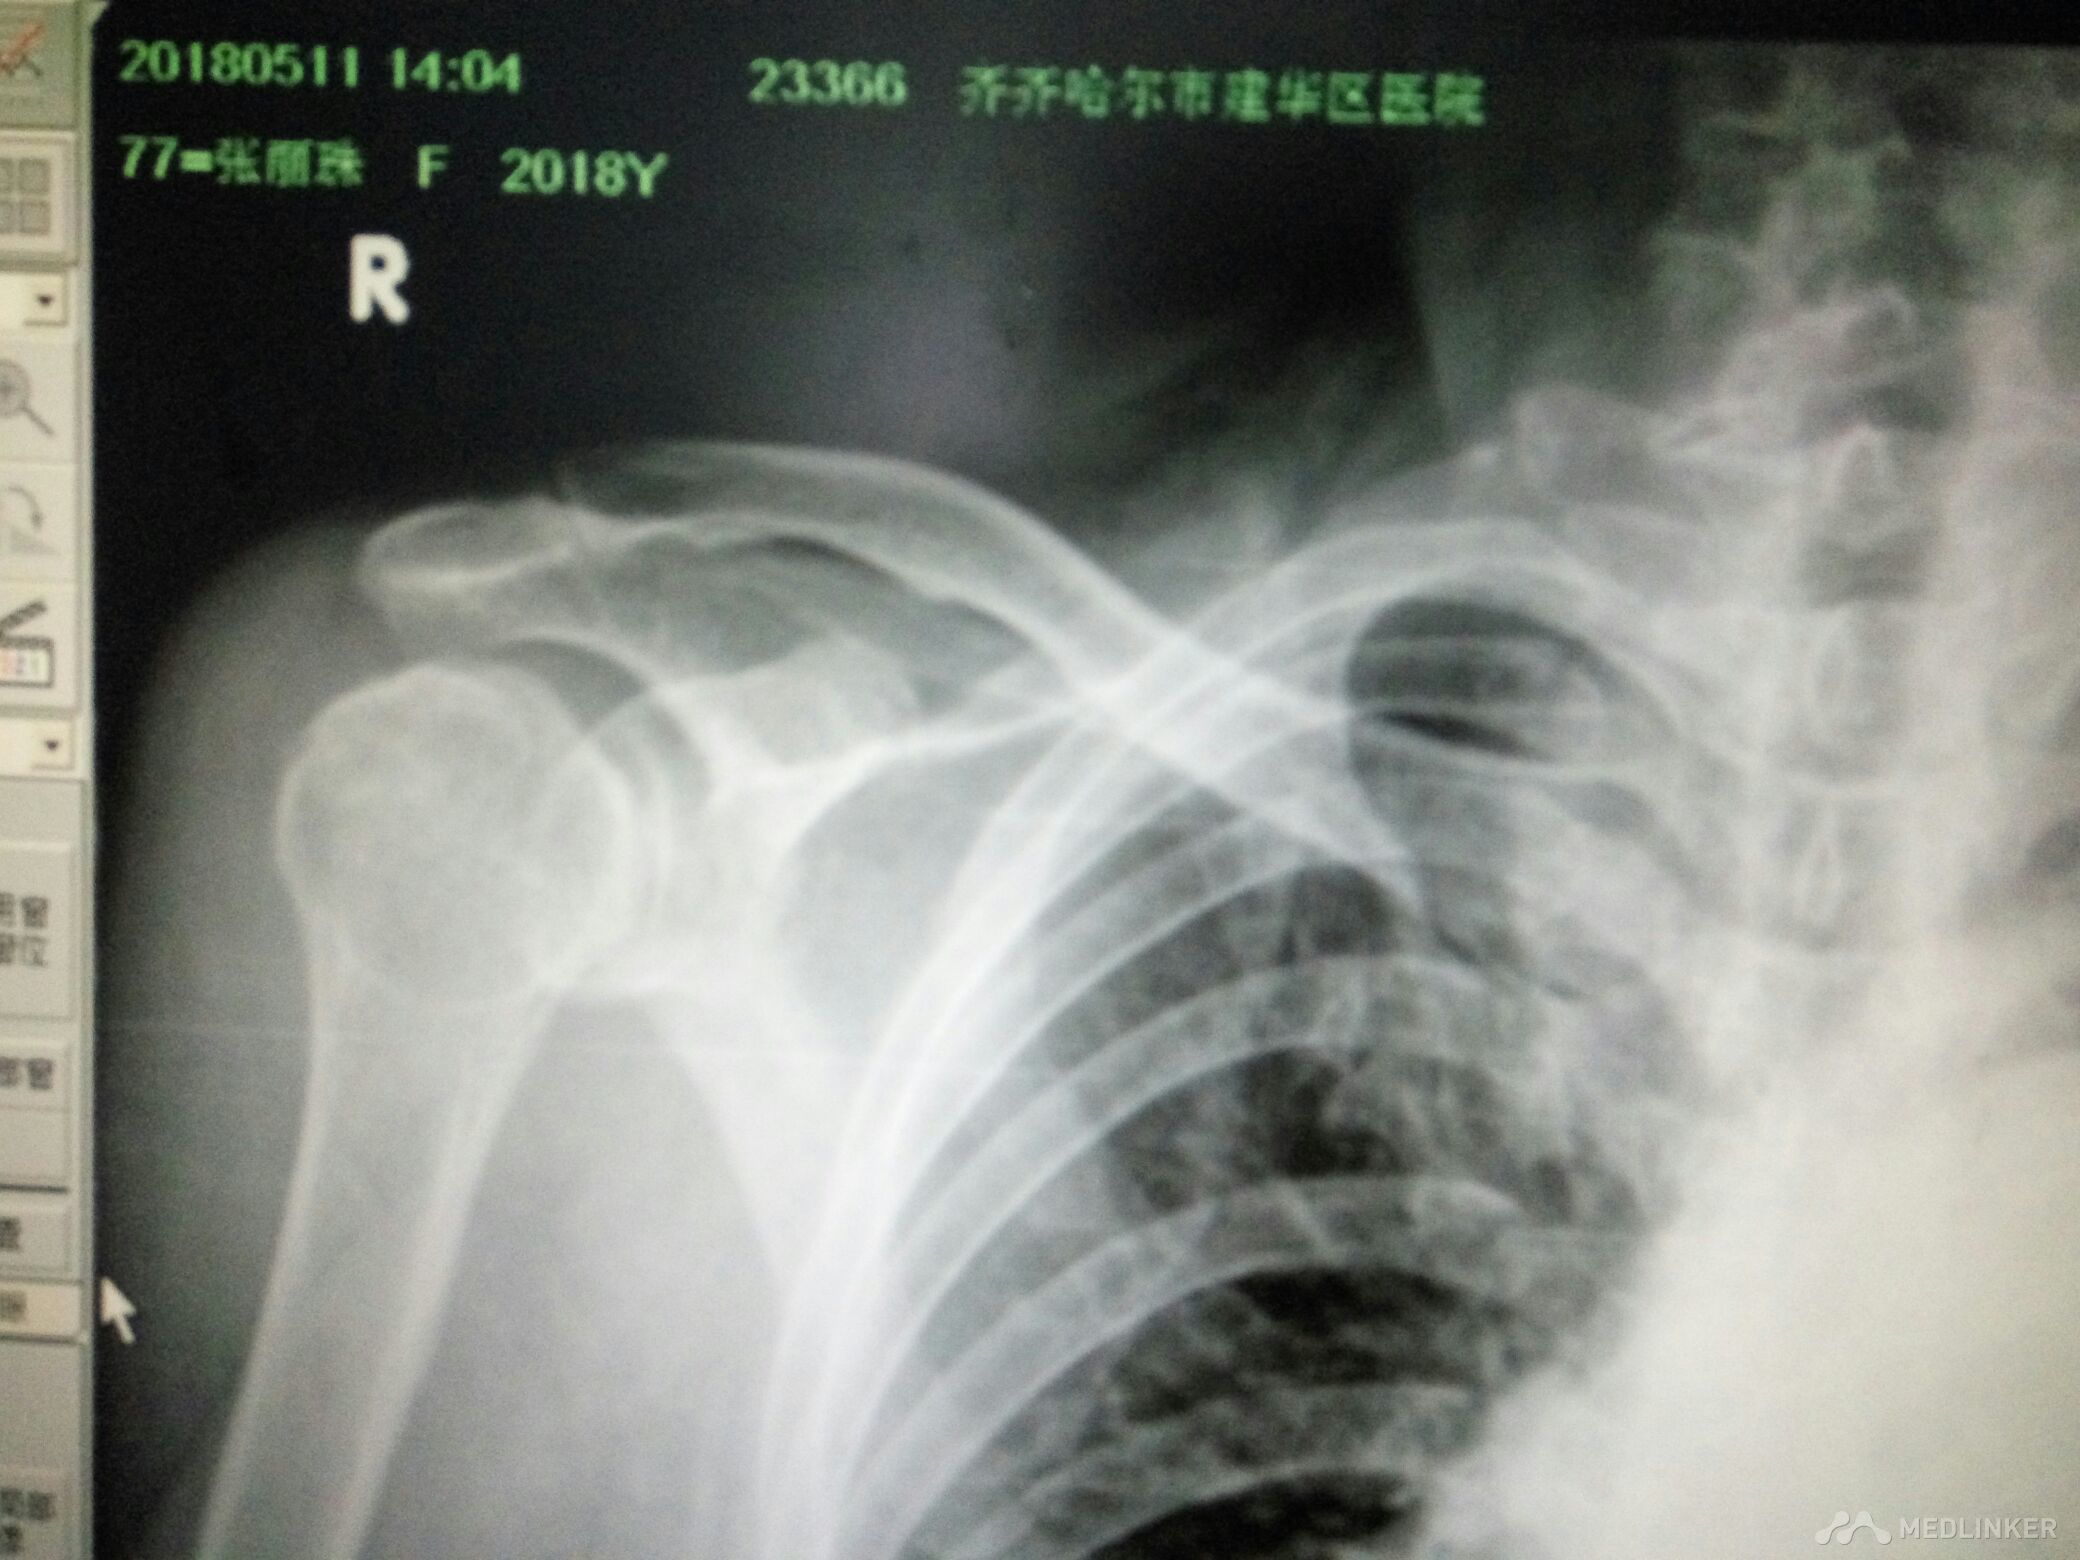

右肩关节脱位并肱大结节撕脱性骨折

该患者女77岁不慎跌倒所致肩关节活动丧失局部疼痛来齐齐哈尔市解放门医院骨科经张立群医生诊断肩关脱位拍片检查右肩关节脱位并肱骨大结节骨折经手法整复后拍片检查复位成功肱骨大结节骨折对位对线良好。